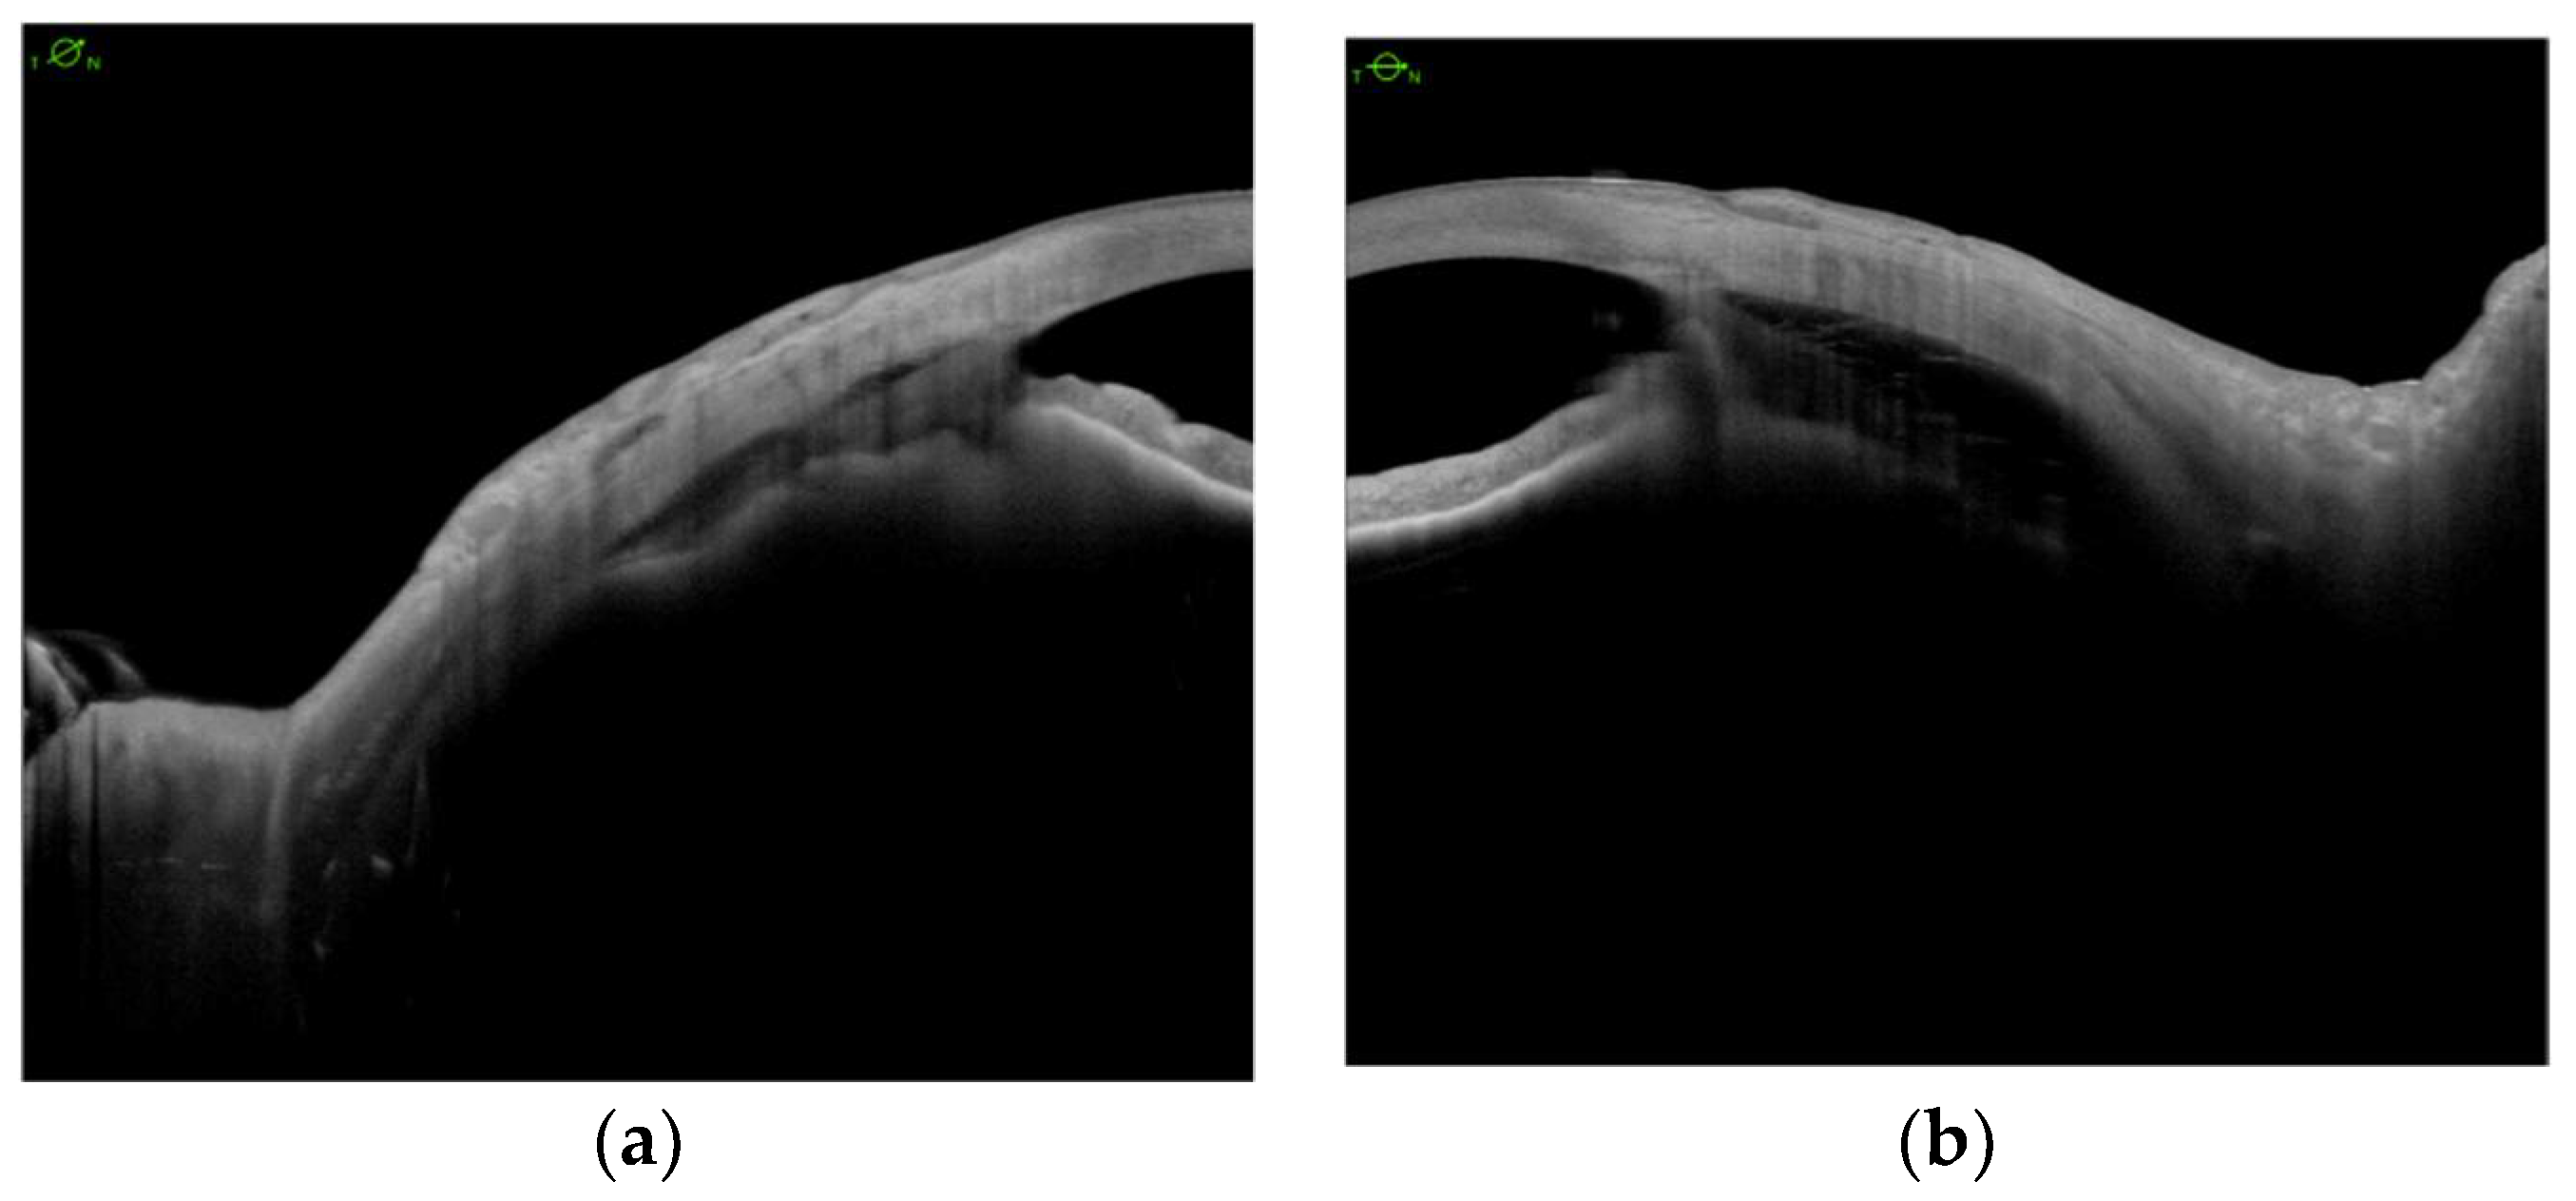

Encircling Scleral Buckling Surgery for Severe Hypotony with Ciliary Body Detachment on Anterior Segment Swept-Source Optical Coherence Tomography: A Case Series

2. Materials and Methods

3. Results